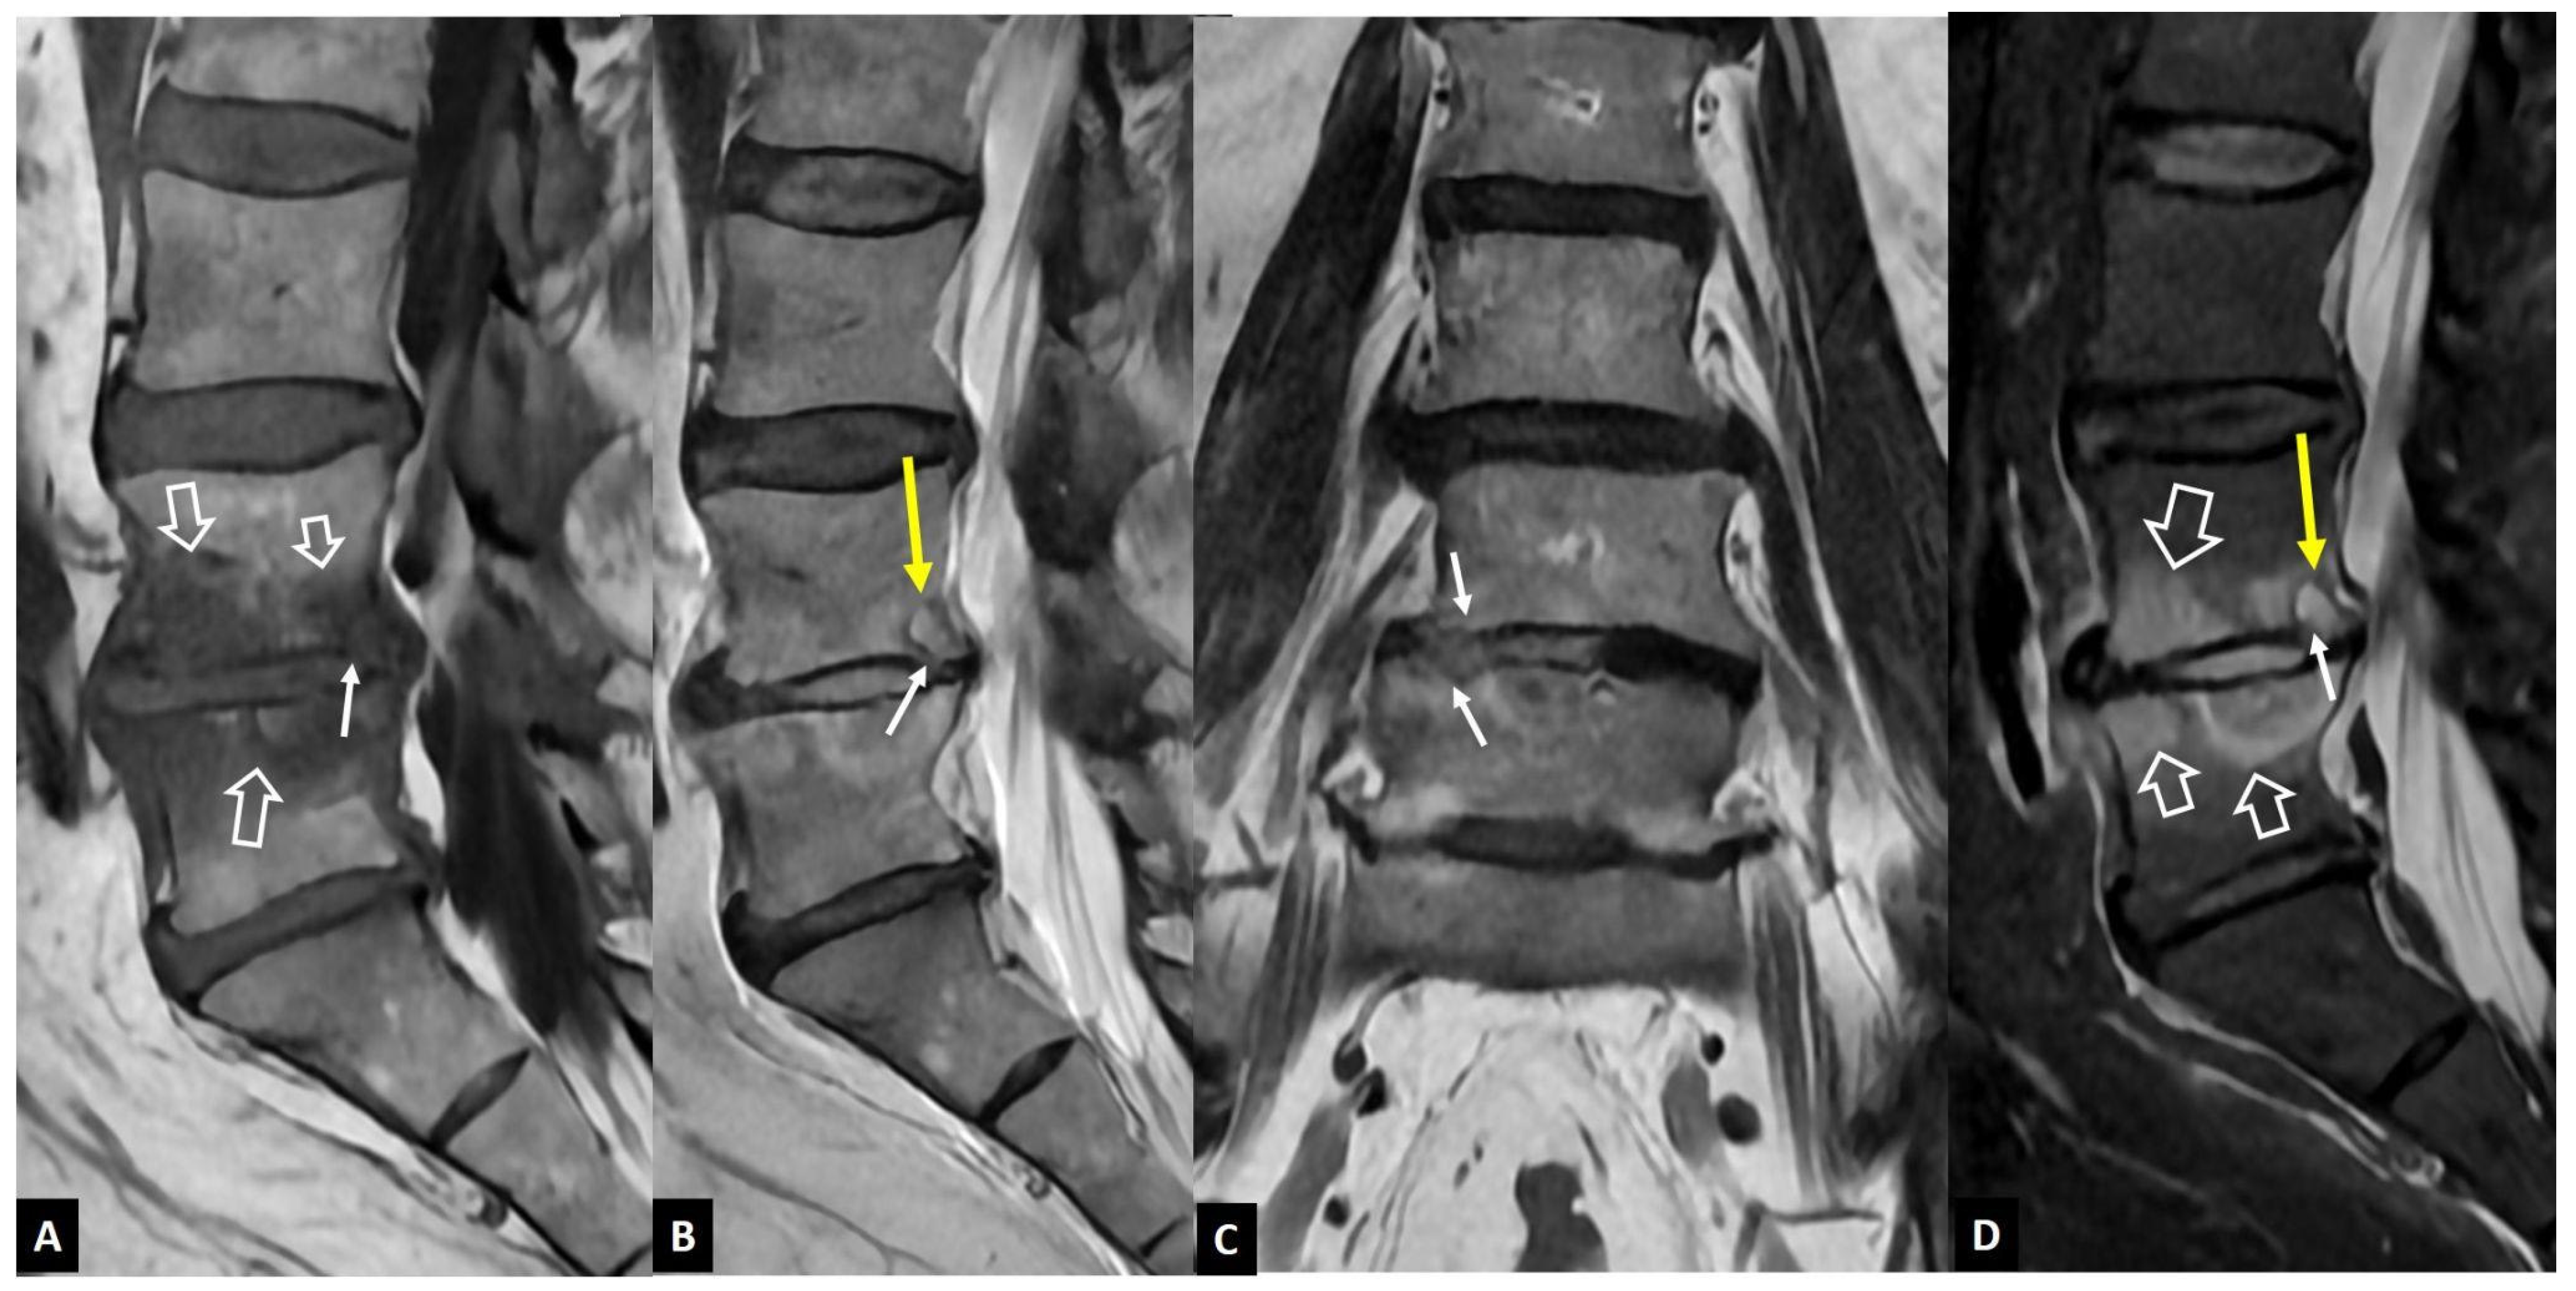

2.1.1. MODIC I Changes

2.1.2. Aseptic Spondylodiscitis

2.1.3. SAPHO Syndrome

2.1.4. Destructive Spondyloarthropathy